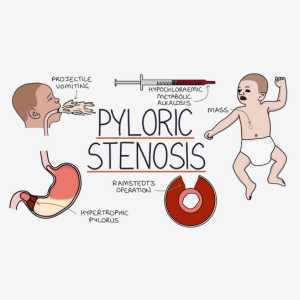

Pyloric Stenosis